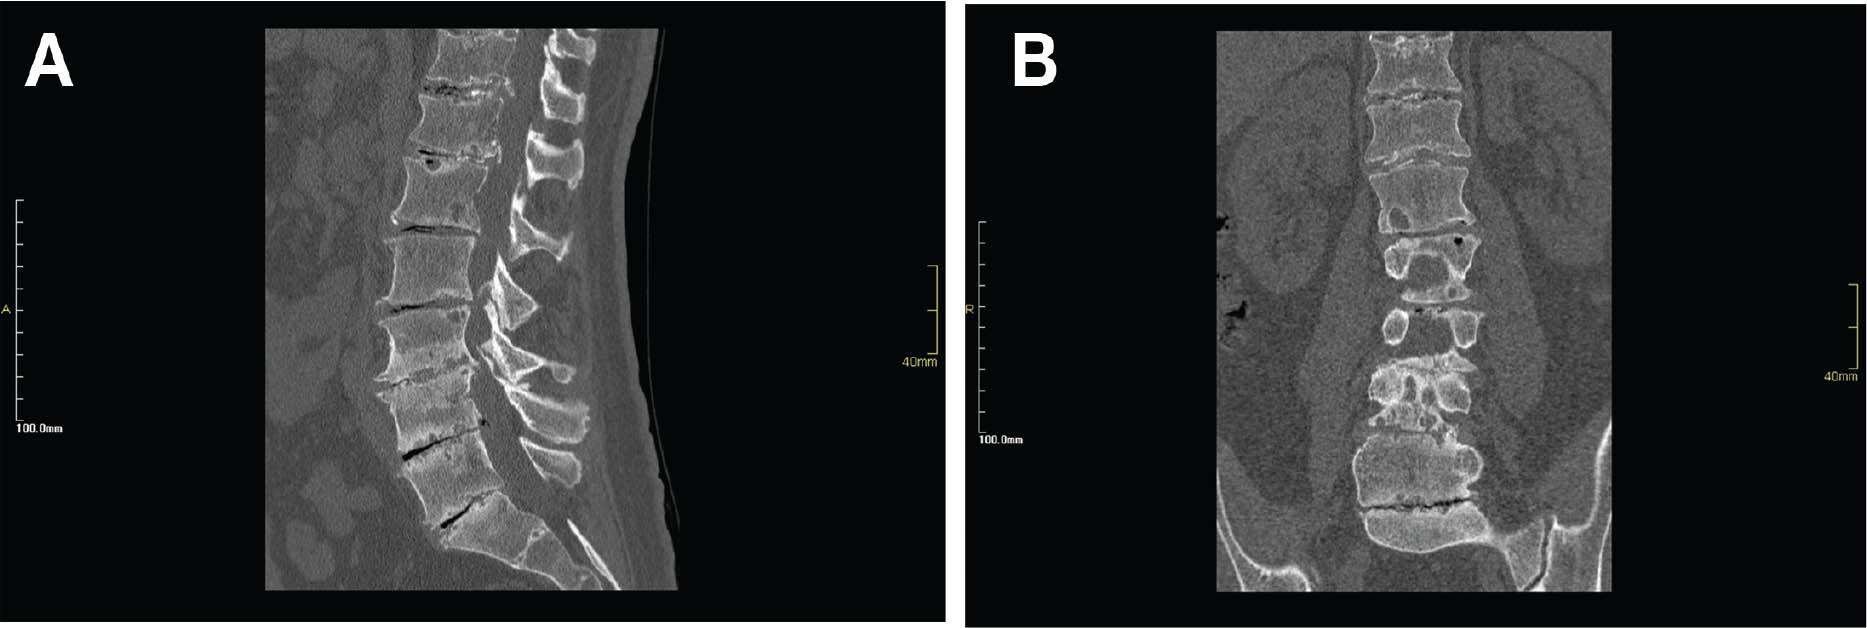

Physical examination revealed a palpable defect over the left Achilles tendon at its insertion. Absence of plantarflexion was observed using a Simmonds–Thompson test. Lumbosacral computed tomography (CT) showed diffuse degenerative changes of the spine (Figure 3). Magnetic resonance imaging (MRI) revealed that the tendinous insertion of the Achilles tendon into the calcaneus tuberosity was completely disrupted with retraction of the proximal part (Figure 4). Surgical exploration through the medial incision to the Achilles tendon down to its insertion site revealed a complete disruption of the tendon at its attachment to calcaneus with fragile, black deposited frayed edges (Figure 5A). The black pigmentation was extensive and reaching the calcaneal tuberosity, extending about 7 cm from the insertion. The excision involved the entire pigmented segment (Figure 5B) and specimens of the fragmented tendon were sent for histopathology with the suspicion of ochronosis. Tendon advancement was not possible due to the large gap created after the excision (>5 cm). A decision was taken to graft the flexor hallucis longus (FHL) tendon (Figures 5C–E). The posterior aspect of the calcaneus was involved in the deposition as well; so, it was challenging to find a healthy area to implant the graft. A suitable area 2 cm anterior to the insertion was prepared after curettage to assure a healthy vascularized bed for the graft. The FHL tendon was forfeited at the Henry knot, and the graft was pulled up through the original incision. With appropriate orientation of the fibers of the FHL tendon, the graft was secured with a conventional screw into the calcaneus. The graft was sufficiently long enough to be sutured over the proximal stump of the Achilles using an absorbable polyglactin 910 suture (Vicryl; Ethicon/Johnson and Johnson). Intraoperatively, a stable plantar and dorsiflexion of the ankle was achieved (Figure 6). Histopathological examination of the resected portion of the tendon revealed a thick fibrosed tendinous tissue with chronic inflammation and focal pigment deposition consistent with the classical features usually seen in alkaptonuria.

Figure 3

Computed tomographic sagittal (A) and coronal (B) reconstruction of the lumbosacral spine showing diffuse degenerative changes represented by disk space narrowing, subchondral cystic changes and erosions, multilevel endplate sclerosis, marginal sydesmophytosis, and the presence of gas in the degenerated disk spaces (vacuum phenomenon). In addition, evidence of disk calcification is noted in the upper disk space level.